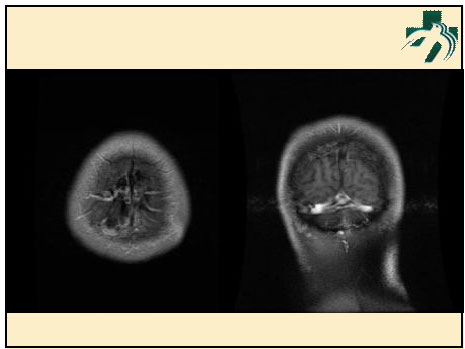

奴卡氏菌感染

第九期三博

读片会

病例之四

北京协和医院 提供

男性,22岁。自觉虫咬后皮疹、肢体麻木4月